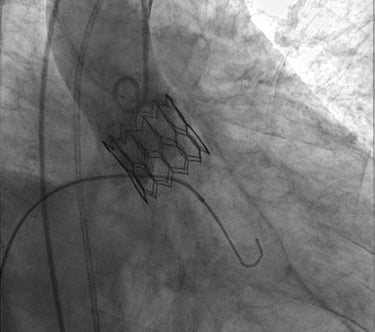

Impianto transcatetere di valvola aortica (TAVI)

Procedura riservata a pazienti che sono affetti da stenosi valvolare aortica severa ma che e’ preferibile non trattare con la chirurgia tradizionale.